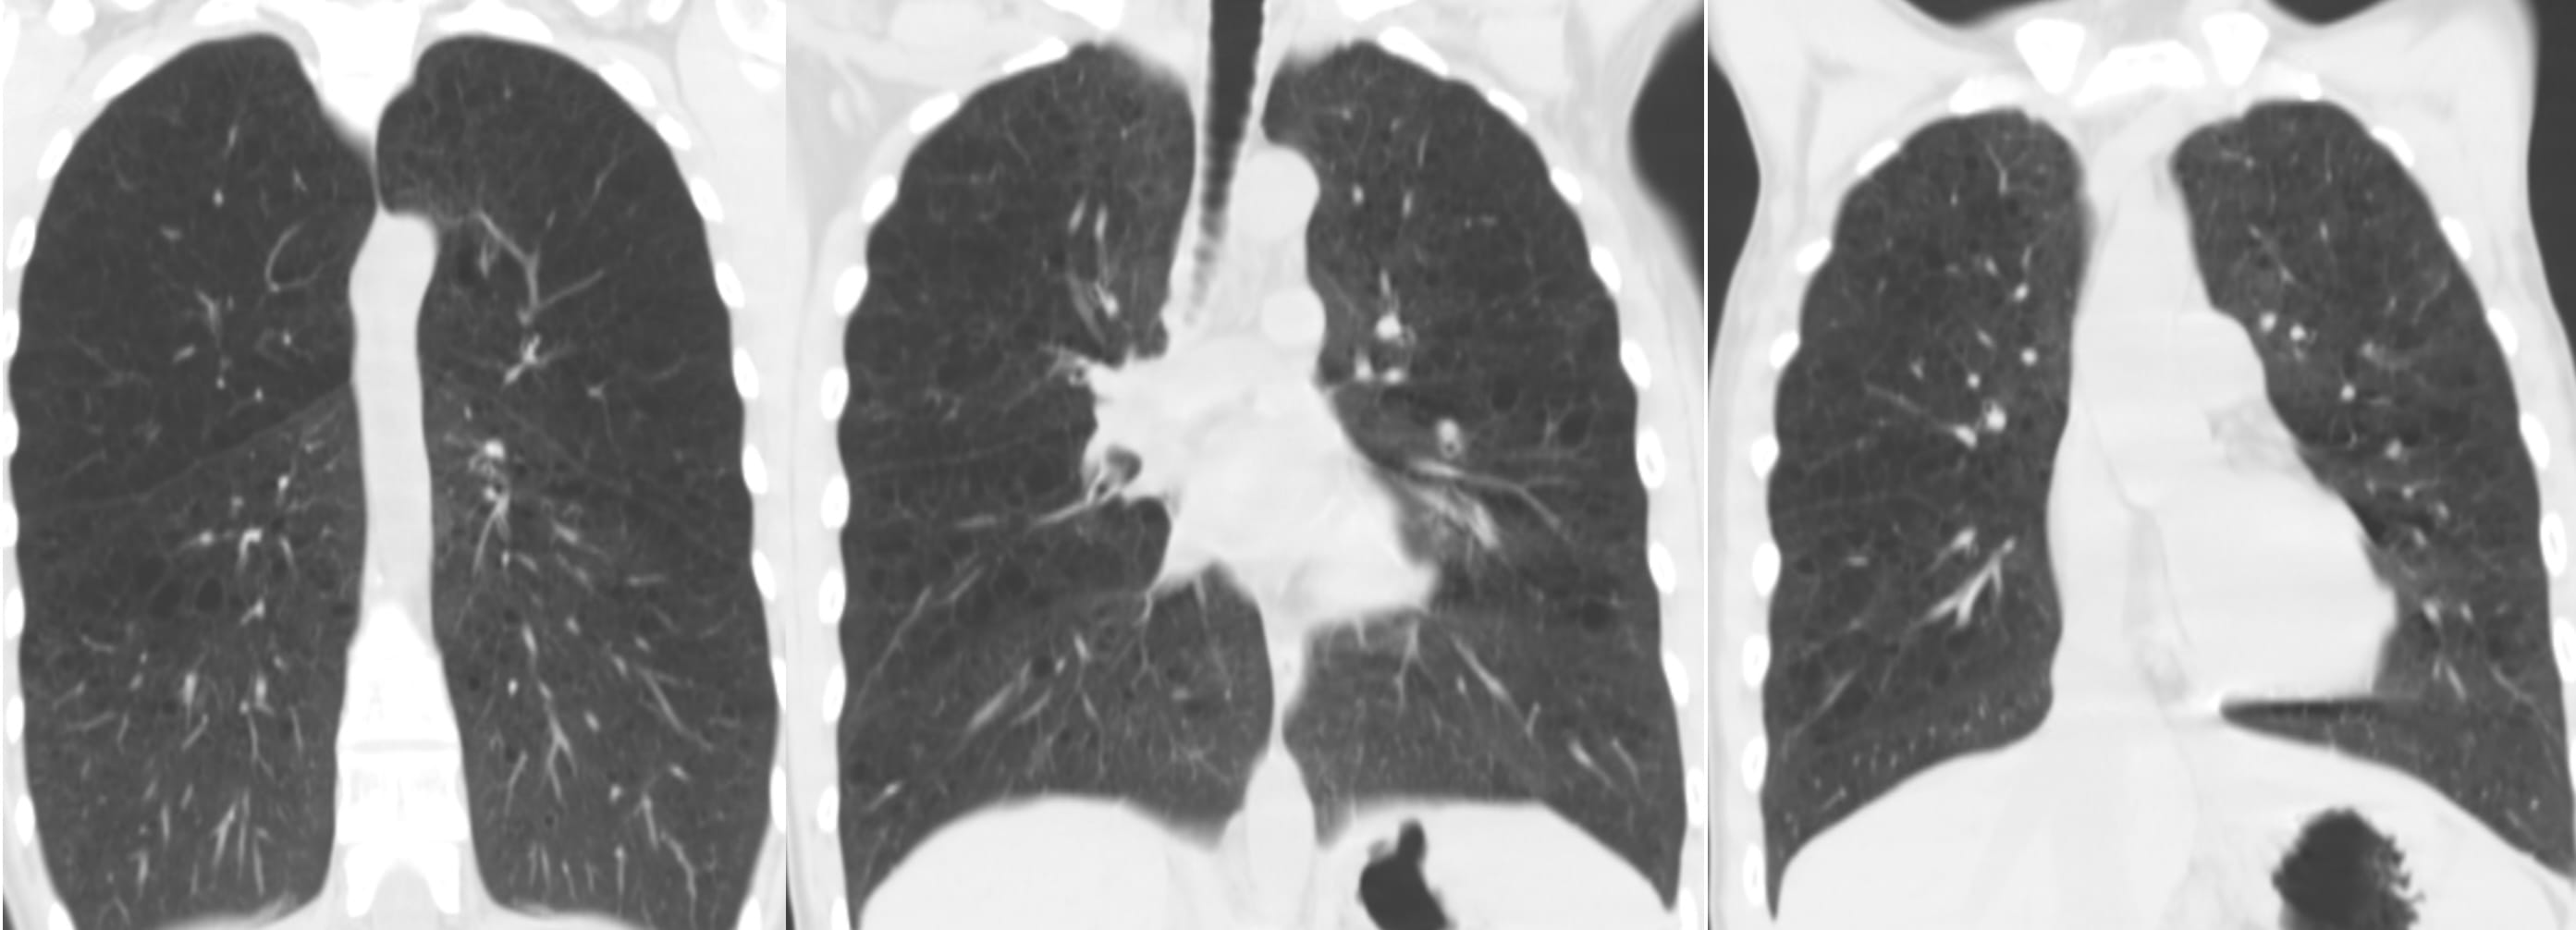

“The cysts’ diameters in AEF are significantly larger than those in UIP and NSIP, but, at the same time, the walls are significantly thinner than those of UIP and thicker than those of centrilobular emphysema (CLE)”

Examples from the article:

One observation seems relevant: the cystic spaces may be situated away from the pleural surface.